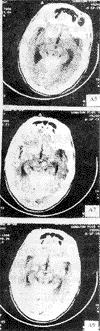

人脑CT(示四叠体)

四叠体(corpora quadrigemina)

又称顶盖,由两对小圆丘组成。上一对,称上丘,由数层相互交替的灰、白质构成,是视觉皮质下中枢,借上丘臂(为白质纤维)与外侧膝状体联系,主要形成眼运动的反射中枢上丘可能接受一般躯体感觉纤维,特别是痛觉纤维。下一对,称下丘,是听觉皮质下中枢,借下丘臂(为白质纤维)与内侧膝状体联系。在每一个下丘内,含有一卵圆形细胞团,称四叠体。